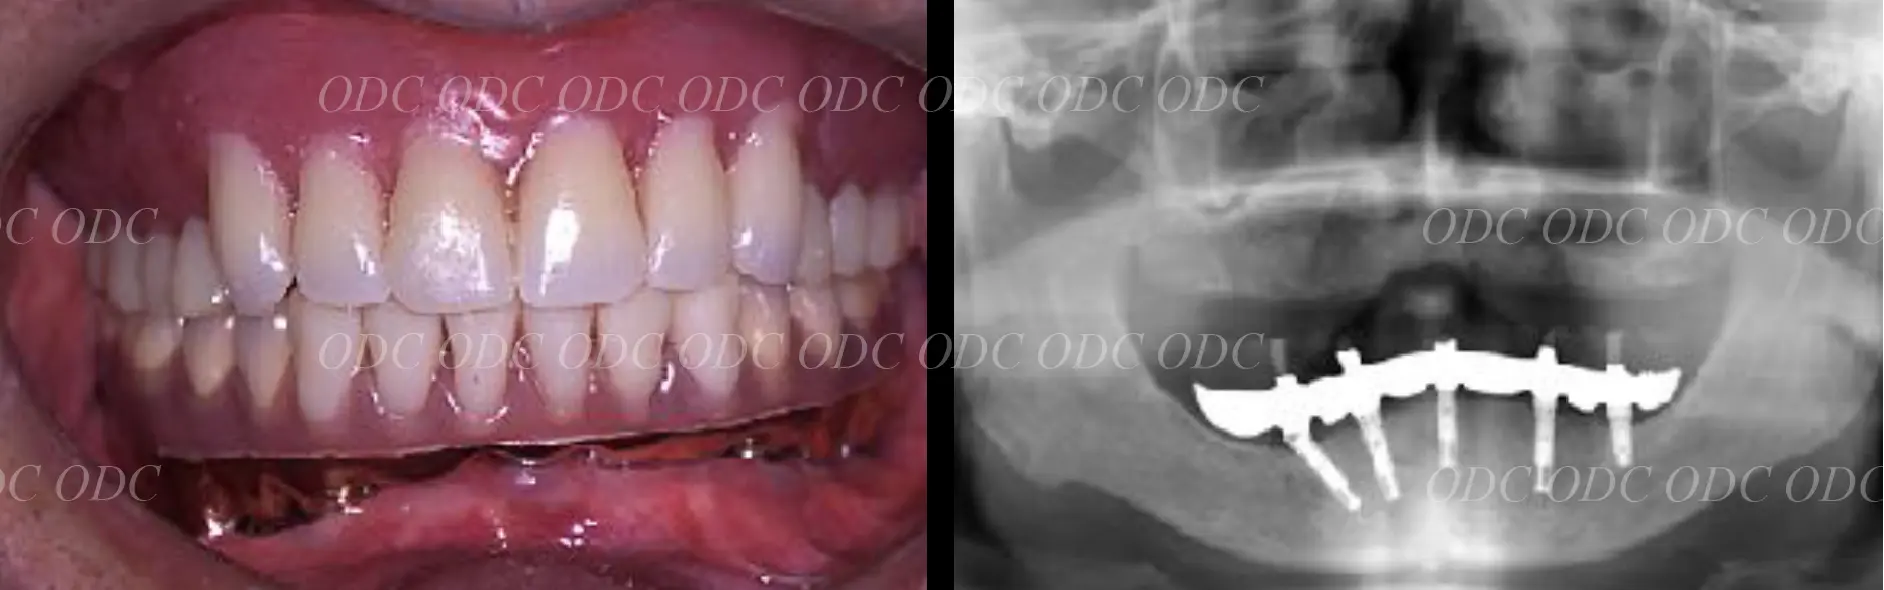

2011年、噛めないという主訴で65歳の男性が来院されました。

全顎的な治療を希望されていましたので、口腔内はもちろん骨格・顔貌・顎関節の診断を行い治療目標を設定致しました。

上顎天然歯に関しては矯正治療、下顎にはフルマウスのインプラント治療を計画致しました。

顎関節の安定を確認した後、矯正治療とインプラント治療を並行して行いました。

約3年の治療期間を経て、計画通りの満足のいく結果を獲得することができました。

2014年、治療終了時の口腔内の状態です。

インプラント上部構造はCADCAMによって作成されたジルコニアの上部構造です。

2024年、治療終了後約10年が経過いたしました。

顎関節を考慮した包括的な治療を行うことで咬合状態(噛み合わせ)は現在もとても安定した状態です。